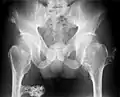

The diagnosis of HMO is based upon establishing an accurate correlation between the above-mentioned clinical features and the characteristic radiographic features. Family history can provide an important clue to the diagnosis. This is supplemented by testing for the two genes in which pathogenic variants are known to cause HMO namely EXT1 and EXT2. A combination of sequence analysis and deletion analysis of the entire coding regions of both EXT1 and EXT2 detects pathogenic variants in 70–95% of affected individuals.[3][7] The hallmark of radiographic diagnosis is the presence of osteochondromas at the metaphyseal ends of long bones in which the cortex and medulla of the osteochondroma represent a continuous extension of the host bone. This is readily demonstrable in radiographs of the knees.[3][1]